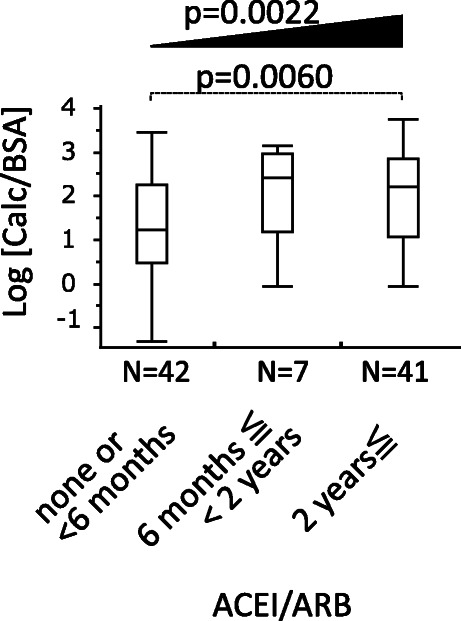

The duration of the use of ACEI/ARB is shown in Fig. 4. Because 31 patients were unknown as to the duration of ACEI/ARB, we excluded these 31 patients in the following analyses and the characteristics of the remaining 90 patients are shown in Table 1B. In 90 patients, group 3 had significantly higher log [Calc/BSA] than group 1 (P = 0.0060) with Tukey-Kramer HSD test. There was a significant trend that the longer the duration of ACEI/ARB, the higher log [Calc/BSA] (P = 0.0022) with Jonckheere-Terpstra trend test. In multivariate linear regression analysis where log [Calc/BSA] was adjusted by age, sex, log [eGFR], and the duration category of ACEI/ARB, the longer duration of ACEI/ARB more than 2 years showed an independent and positive association with log [Calc/BSA] (model A, Table 3). Even after the further adjustment by the various factors such as phosphate, DM, hypertension, dyslipidemia, diuretics or malignancy as in model B, model C and model D, ACEI/ARB treatment in Group 3 seems to consistently contribute to higher log [Calc/BSA] by 0.2268 to 0.2864 as compared with the reference group (Table 3).

Fig. 4.

Time duration association of ACEI/ARB and vascular calcification volume. Patients using ACEI/ARB were categorized into three groups according to the duration time. Thirty-one patients were excluded from the analysis because of unknown duration time. Tukey-Kramer HSD test shows that the longest duration Group 3 has higher log [Calc/BSA] than the shortest Group 1 (p = 0.0060). Jonckheere-Terpstra trend test shows statistically significant increment of log [Calc/BSA] in accordance with the duration time (p = 0.0022). ACEI, angiotensin-converting-enzyme inhibitor; ARB, angiotensin II receptor blocker; BSA, body surface area calculated with Fujimoto’s formula; Calc, calcification volume